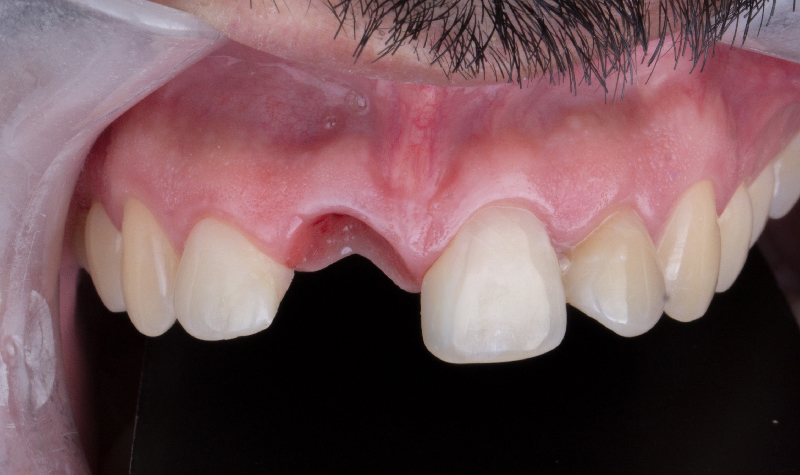

Prótesis híbrida superior de cerámica fija sobre implantes.

Prótesis híbrida superior de cerámica fija sobre implantes